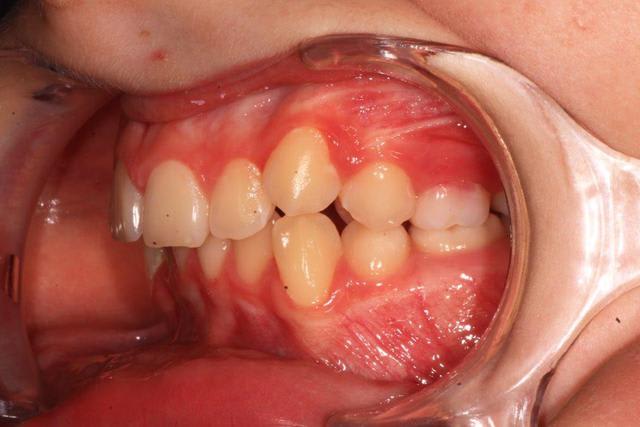

jeune homme de 12 ans 1/2 , consulte pour luxation atm et demande de gouttière.

Au niveau ODF , il y a une cl 2 bout a bout avec supra, malposition canine.

quelques documents :